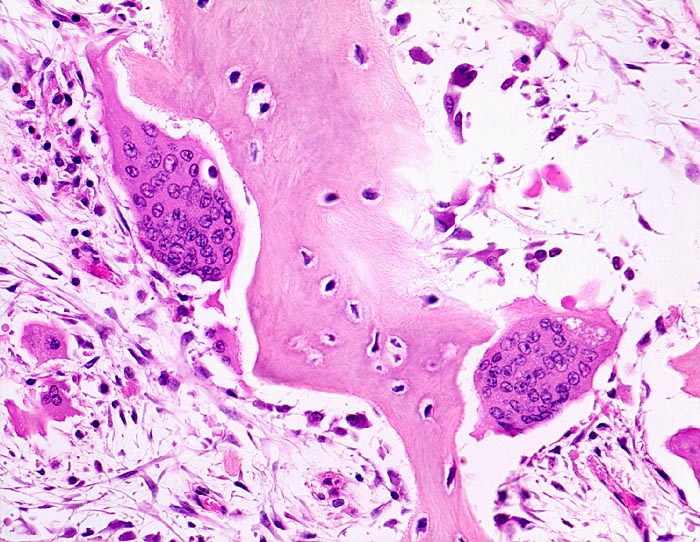

• Riesenosteoklasten mit über 20 Kernen sind an der Knochenoberfläche erkennbar.

An den betroffenen Stellen ist sowohl der Knochenabbau als auch der Knochenanbau gesteigert. Die Osteoklasten sind auffallend gross und enthalten sehr viele Kerne (> 3518). Die aktivierten Osteoblasten produzieren verdickte und grob geflochtene Spongiosabälkchen. Der neugebildete Knochen ist strukturell und morphologisch abnorm und schlecht mineralisiert. Der Knochen wird dadurch weich und anfällig auf Frakturen oder Deformation unter Belastung (nach vorne gebogene Säbelscheidentibia). Das Knochenmark wird ersetzt durch fibrovaskuläres lockeres Stroma, welches an Granulationsgewebe erinnert. Mikroskopisch werden eine osteolytische Initialphase, eine Umbauphase mit verstärkter Knochenneubildung und eine sklerosierende Stabilisationsphase mit strukturellem Umbau und Spongiosierung der Kortikalis (verbreiterte spongiosaartige Kortikalis) unterschieden.

• Die Spongiosabälkchen sind auffallend verdickt, vermehrt und unregelmässig geformt.